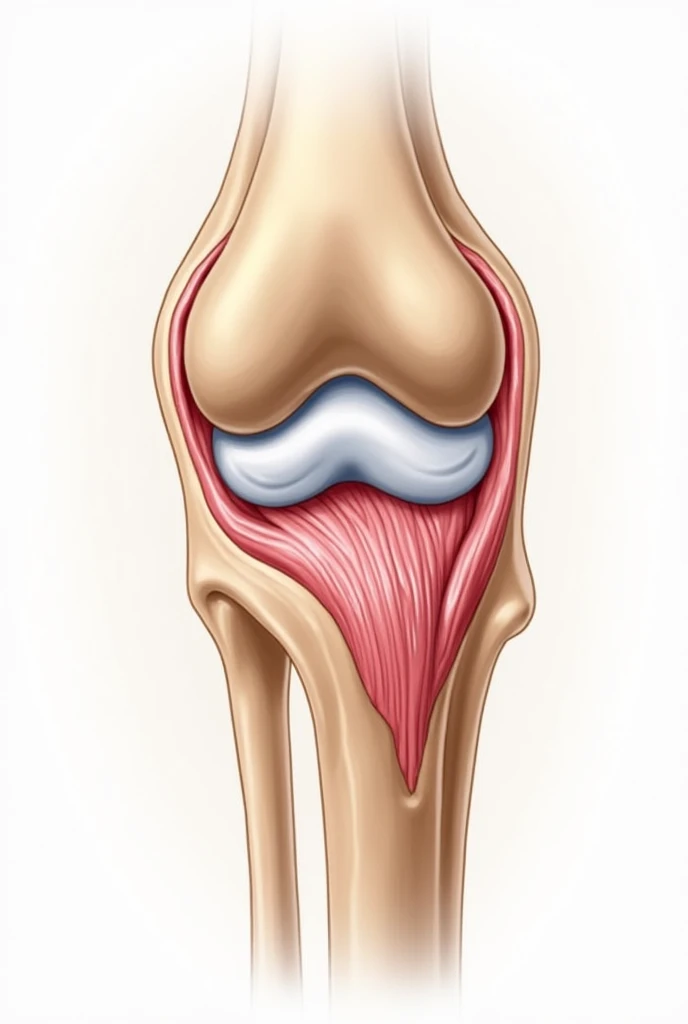

A close up of a white object with a human leg

Close-up of human knee,There is a bone in the middle, knee, Knees, surreal bone structure, Protruding bones, Realphotos, orthographic view, Look across the shoulder, medical depiction, Osteoarticular joints, computer generated, hyper realisitc, sharp bone structure, joint, digital painted

medical depiction

Osteoarticular joints